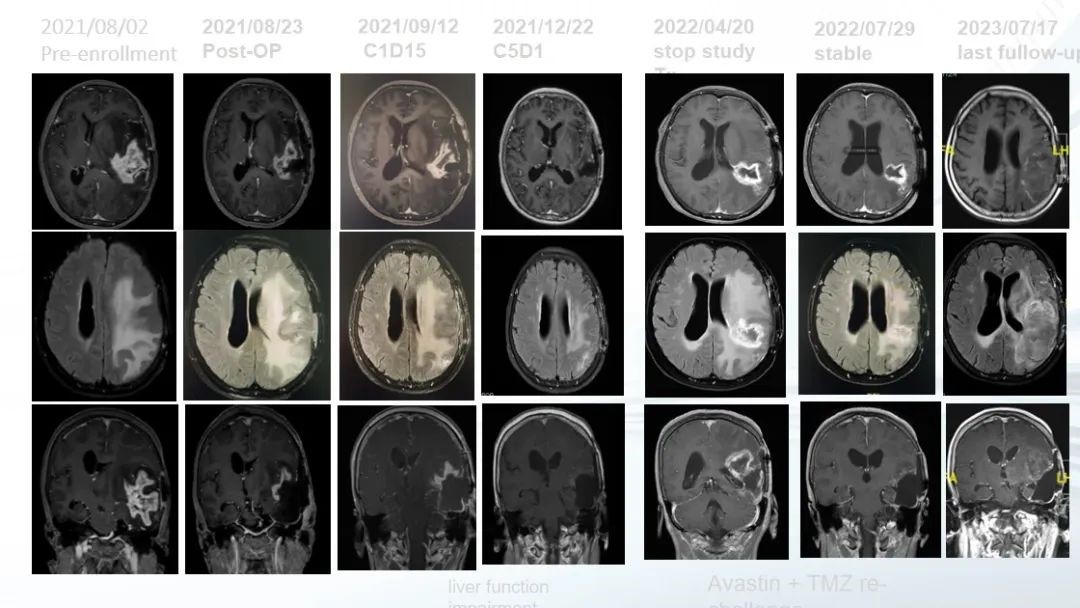

典型病(bing)例(li)分享

患(huan)者,女(nv),59歲。

2020年12月(yue)14日

首次手術病理證實為GBM(IDH 野(ye)生型,TERT突變),放療同步替莫唑胺(TMZ)加(jia)后續化療5個月后復發。

2021年(nian)8月

入(ru)組本(ben)研究治療,術前給(gei)予卡(ka)瑞利(li)珠單抗及阿(a)帕替尼(ni);2021年8月(yue)18日再次(ci)手術,證(zheng)實為復發。后(hou)(hou)續7個周(zhou)期(7個月(yue))研究性治療,腫瘤CR。后(hou)(hou)因出現肝功能異常退(tui)出研究性治療。

2022年改(gai)為貝伐珠單抗加(jia)TMZ小劑量方案。至2023年7月(yue)(末次隨訪)腫瘤(liu)穩(wen)定。患者自首次診斷生存(cun)(cun)已51個(ge)月(yue),入(ru)組本研究治療后生存(cun)(cun)已24個(ge)月(yue)。

圖.病例的影像資料